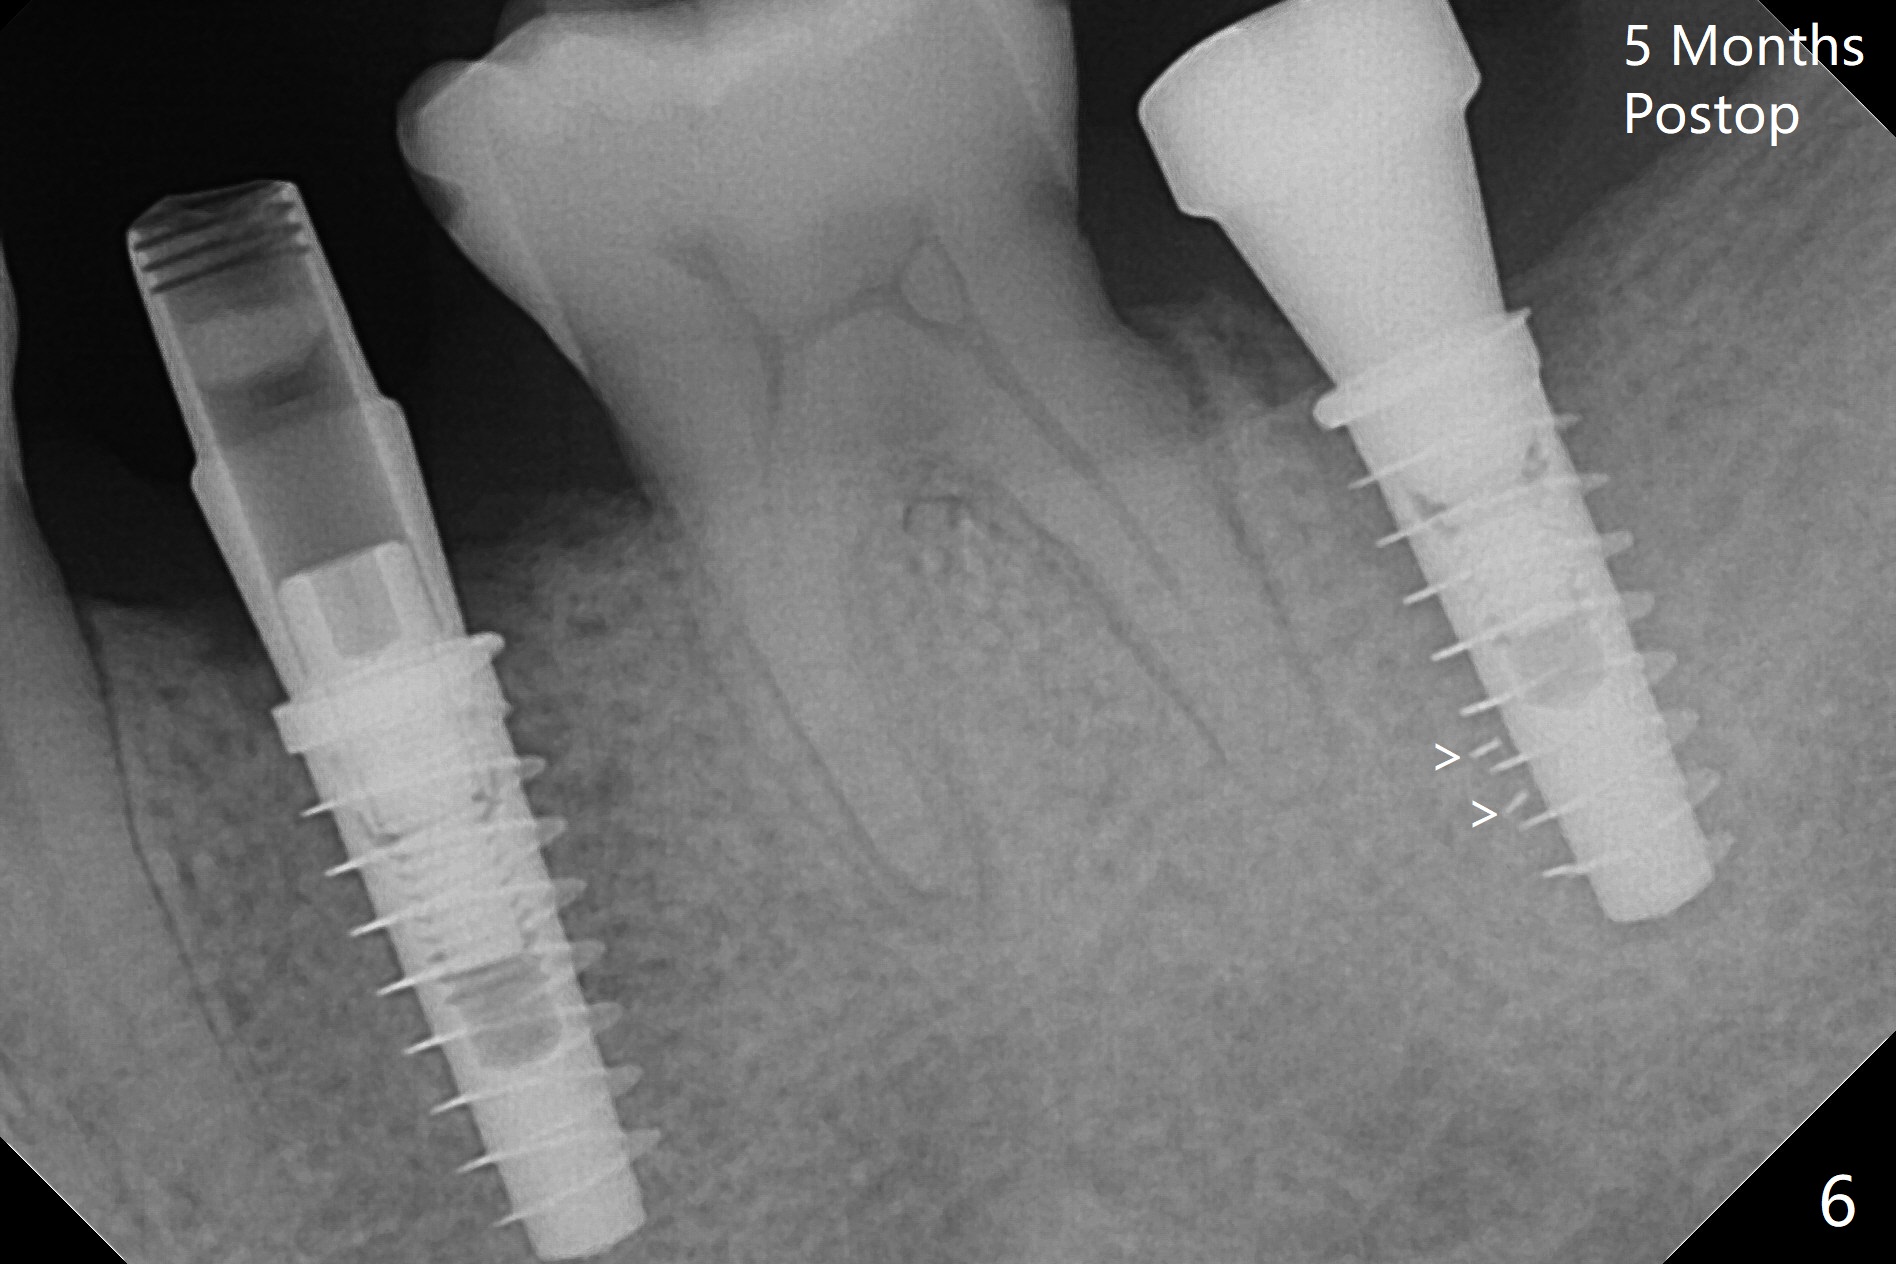

为了预防钻头遇到舌侧骨板而往颊侧偏移,有意不拔除第二前磨牙牙根。但是2.2毫米钻头钻洞很吃力,最后不得不拔除牙根,阻力骤然减少,顺利完成植入,而且颊侧间隙还够(图一,二),填入骨粉后远中螺纹间空间消失(图三箭头)。今后最后一个钻头完成钻洞后留在原位,周围放置适当量的骨粉,然后取出钻头,植入植体,这样空间可以比较全面充填。即刻种植没有颊侧偏移可能是因为设计时植体没有过多接触舌侧骨板(图四L)。第二磨牙延期种植需要切开是因为颊侧角化牙龈不足。术后两个月,前磨牙植体顶端似乎被牙槽嵴覆盖了(图五 *)。术后五个月,旋转7愈合基台,下面植体疼痛,可能与植体螺纹断裂有关(图六:>),5取模。